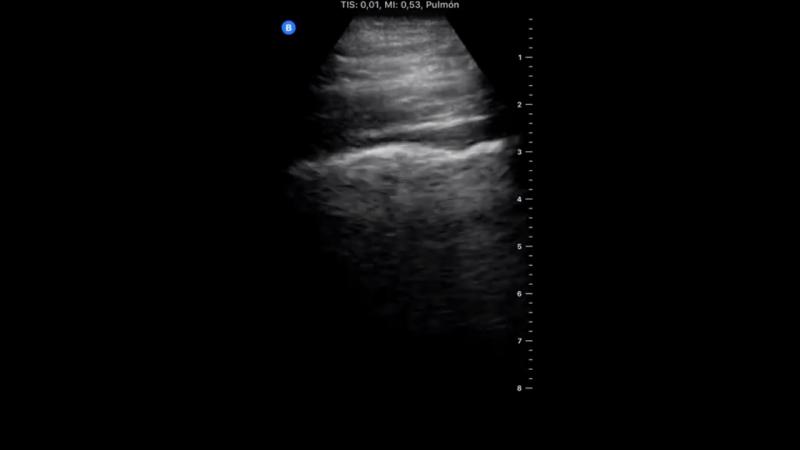

În cea de-a treia zi de la diagnosticul COVID-19, medicul a scris că nu mai avea durere în gât ori durere de cap. A fost chinuit de tuse, fără dificultate în respirație sau durere în piept. „A început diareea, tusea a început să mă lase. Aceleași modificări la plămâni”, a mai scris el.

Plămânii doctorului Yale Tung Chen, în a treia zi după diagnosticul COVID-19.